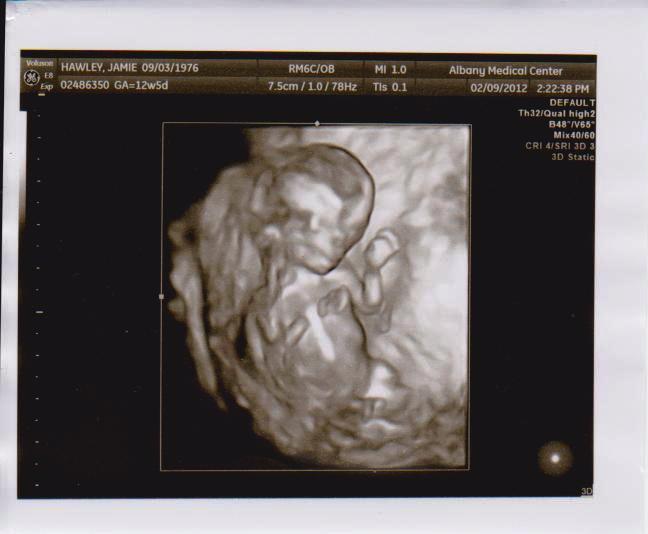

Great Expectations A 4d Ultrasound Experience Albany Georgia